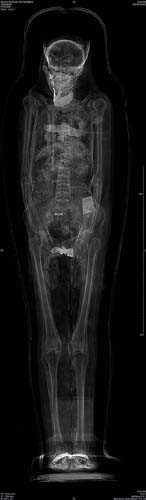

2. Fotoğrafta gördüğünüz Mısır mumyasının CT taraması, uygarlığının gizemlerini çözmeye yardımcı olacak.

Fotoğrafta gördüğünüz Mısır mumyasının CT taraması, uygarlığının gizemlerini çözmeye yardımcı olacak.

3. İngiltere'de Dr. Abeer Helmi, bu teknolojiyi kullanarak tarihin derinliklerinden gelen lahitleri açarken zarar verme riski olmadan içeriğini görüntüleyebiliyor.

İngiltere'de Dr. Abeer Helmi, bu teknolojiyi kullanarak tarihin derinliklerinden gelen lahitleri açarken zarar verme riski olmadan içeriğini görüntüleyebiliyor.

4. Dr. Helmi, British Museum'dan özel izinle aldığı yedi mumya üzerinde bu cihazı test etti.

Dr. Helmi, British Museum'dan özel izinle aldığı yedi mumya üzerinde bu cihazı test etti.

5. Yapılan taramalar M.Ö. 900 civarında Mısırlıların sağlığı ve davranışları konusunda önemli ipuçları verdi.

Yapılan taramalar M.Ö. 900 civarında Mısırlıların sağlığı ve davranışları konusunda önemli ipuçları verdi.